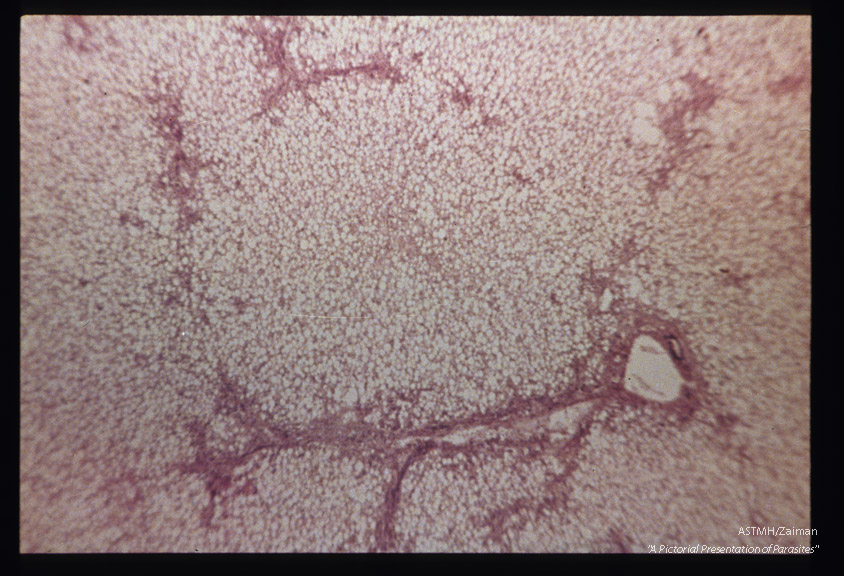

Hematoxylin-eosin stained section of above liver showing fatty degeneration of parenchymatous cells.

Description: Hematoxylin-eosin stained section of above liver showing fatty degeneration of parenchymatous cells.